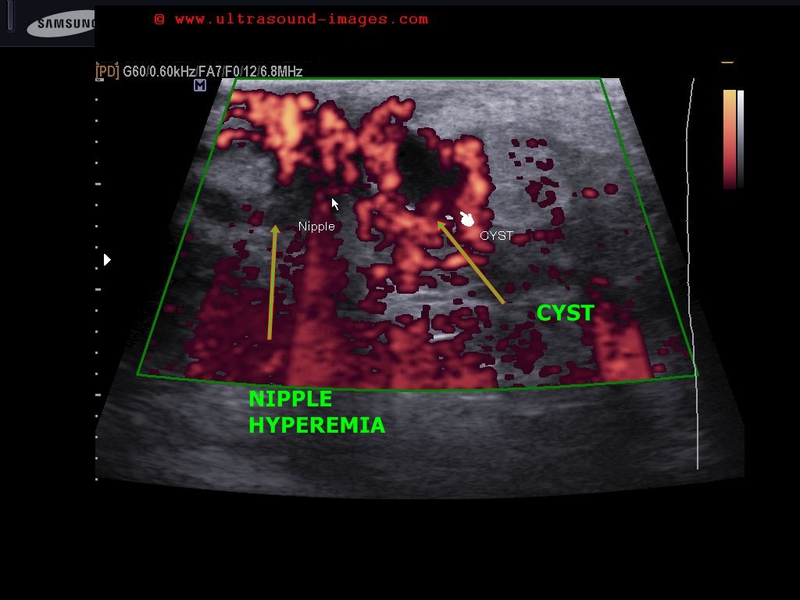

They can occur at any age, and in any part of the body, but most commonly arise on the skin, liver, breast. I went to the hospital yesterday to get an ultrasound done on a breast lump and I know they aren 39t supposed to tell you anything until you see a doctor but she left the room and. Breast vascular tumors - Moose and Doc Vascular Breast tumors: angiolipoma and hemangioma Vascular means related to blood vessels, so a vascular or vascularized tumor is one which contains many blood vessels and is richly supplied with ere are often increased vascular components in many different kinds of breast tumors, including breast cancer tumors, but the classification of vascular breast tumors. Org Sep 1 20Vascular or lymphatic system invasion happens when breast cancer cells break into the blood vessels or lymph channels.

East hemangioma is a benign vascular tumor with a frequency of as much as in postmortem specimens (20). These lesions are classified as capillary or cavernous hemangiomas, depending on the size of their. Anatomically, breast tissue is located between the anterior and posterior layers of the superficial pectoral fascia.Lesions located superficial to the anterior pectoral fascia in the subcutaneous fat are extraparenchymal in origin with or without dermal involvement.

This increases the risk of the cancer traveling outside the breast or coming back in the future. If a patient has a history of pregnancy and lactation an abscess is classified as a puerperal abscess. Jan 2 20This Site Might Help You. Vascular Tumors - PubMed Central (PMC) Angiosarcomas (ASs) are rare and aggressive vascular tumors, rapidly proliferating with extensively infiltrating anaplastic cells derived from blood vessels and lining irregular blood-filled spaces. Benign vascular tumors of the breast include hemangiomas, lymphangiomas, and angiolipomas.